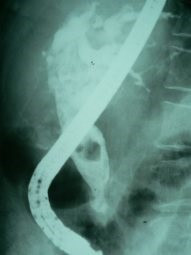

Cálculo gigante ERCP

Envíado por Dr. Carlos Miguel Zavaleta Consuegra